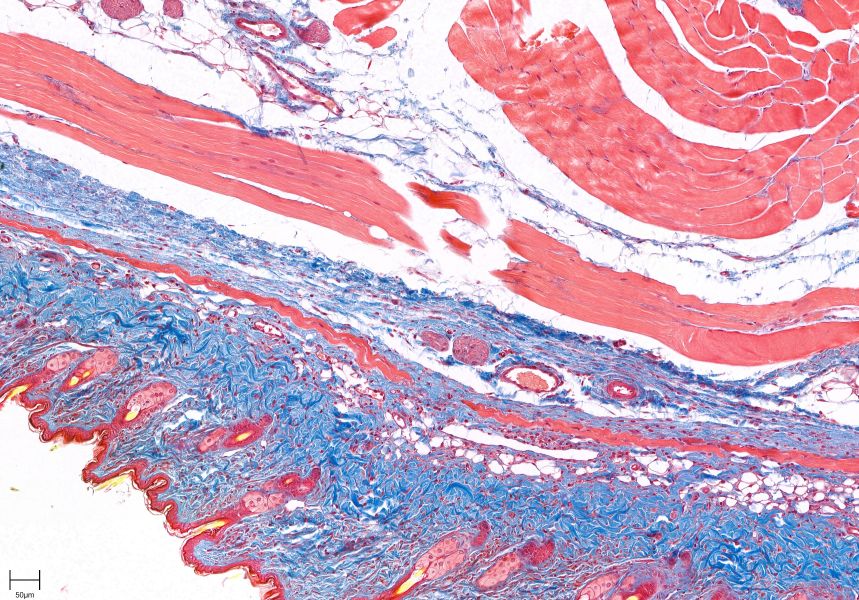

Masson染色